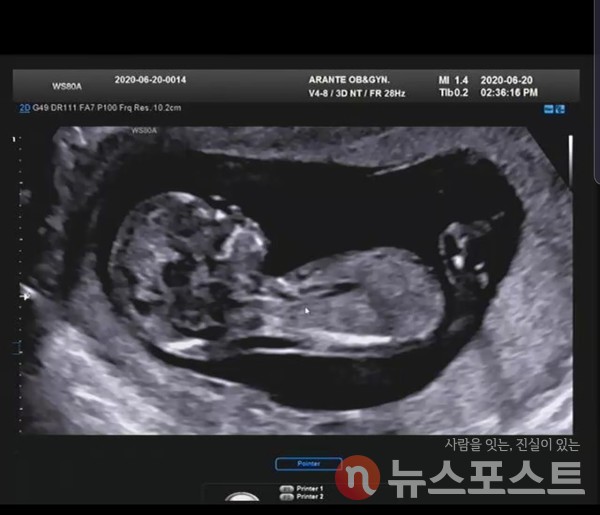

[뉴스포스트=이해리 기자] 늦은 결혼과 출산 등의 영향으로 자연스럽게 난임 인구가 증가하고 있다. 우리나라 부부 7쌍 중 1쌍이 난임을 겪을 정도로 난임은 더 이상 개인의 문제가 아닌 사회적 문제로 인식되고 있다.

난임이란 1년간 피임하지 않고 정상적인 부부관계를 해도 임신이 이뤄지지 않는 경우를 말한다. 일반적으로 결혼 후 임신 가능성은 1년 이내에 85%, 2년 이내는 95%로 보통 1년 정도 임신 시도를 했지만 성공하지 못한 경우 난임 검사를 받길 권유한다.

일반적으로 자연 임신이 가능한 경우라면 자연임신의 확률을 높이도록 ‘배란유도’ 등의 방법을 사용한다. 이 방법으로 임신이 성공하지 못한다면 남성의 정자를 농축시켜 자궁 안쪽에 주입하는 ‘인공 수정’ 방법 등 임신 확률이 더 높은 방법을 사용한다. 이후에는 난자를 채취해 외부에서 남성의 정자와 수정을 시켜 배아를 만들고 다시 자궁에 이식하게 하는 ‘체외 수정(시험관 시술)’ 방법을 시도한다.